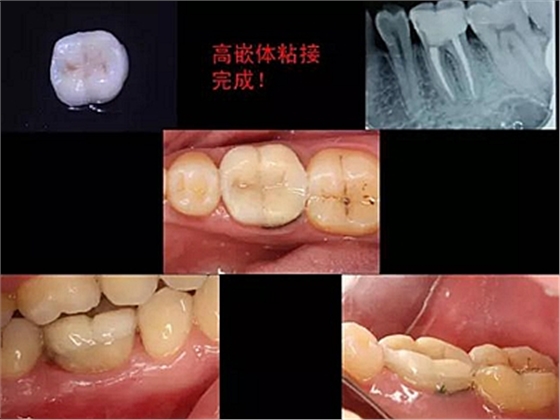

一周后拆除縫線,試戴高嵌體,試戴合適后雙固化粘結(jié)。調(diào)合,拋光。

冠延長手術(shù)和高嵌體修復(fù),本來需要很多次復(fù)診的患者,兩次就診,就把患者難以處理的問題輕松解決了。減少了患者的就診次數(shù)和時間。